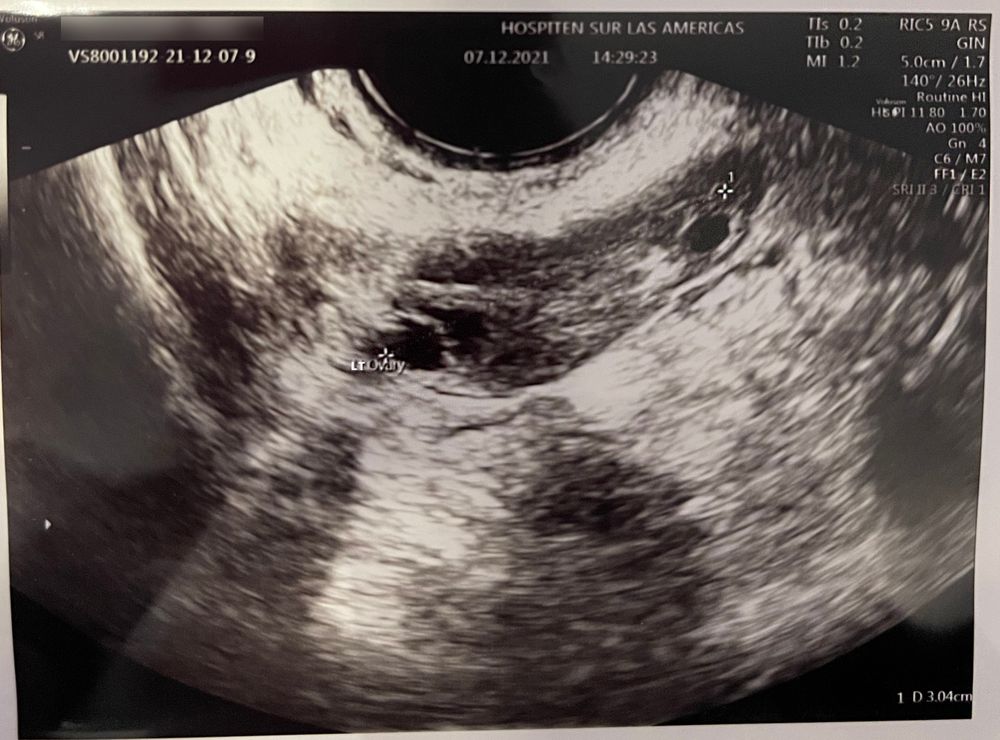

Узи яичников, овуляция

Работаем над зачатием ребеночка третий цикл, прошлый месяц фолликулы были недозревшие, без овуляции. в этом цикле тоже загадка, была овуляция или нет. Видно ли, что зреет доминантный ф?

Дата этого узи 07.12.21 (это 8 день цикла). Есть ли надежда что овуля все-таки была? Врач пока не хочет отслеживать этапность роста фолликулов, сказал сдать сначала анализы и потом будет смотреть, что дальше делать.

Левый яичник